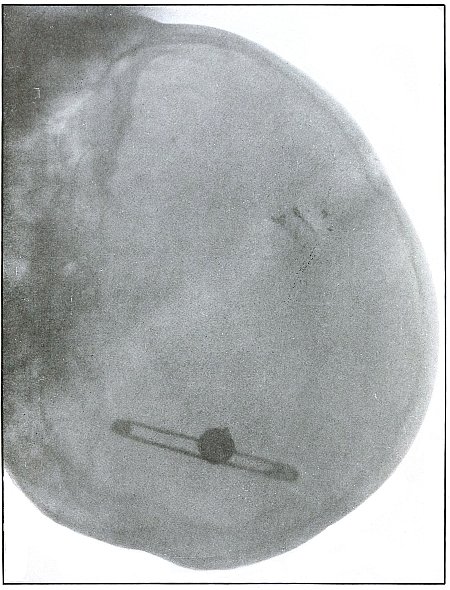

PELVIS.

Plate 46.

[Pg 103]

Rifle—Plate 46.

PELVIS.

Gunshot Wound of the Pelvis,

with Lodgment of the Missile in the Abdomen.

The course of the bullet was from behind forward, striking the crest

of the ilium, on which it was deflected, and spattering off some lead

fragments. The slight penetration indicates a velocity of extremely

long range and a striking energy lessened by ricochet.

The irregular outline of the shadow of the projectile shows its

deformity, and the blurred outline indicates intra-abdominal movement

with respiration.

While the missile, as revealed by its shadow, is not a shrapnel ball,

the distribution of lead particles is more suggestive of a shrapnel

than of a rifle projectile, and the ballistic conditions are more

characteristic of the former than of the latter.

There was no abdominal reaction; the invasion of the abdomen was

revealed by the radiograph.

The treatment in such cases is noninterference unless subsequent

developments furnish definite indications.